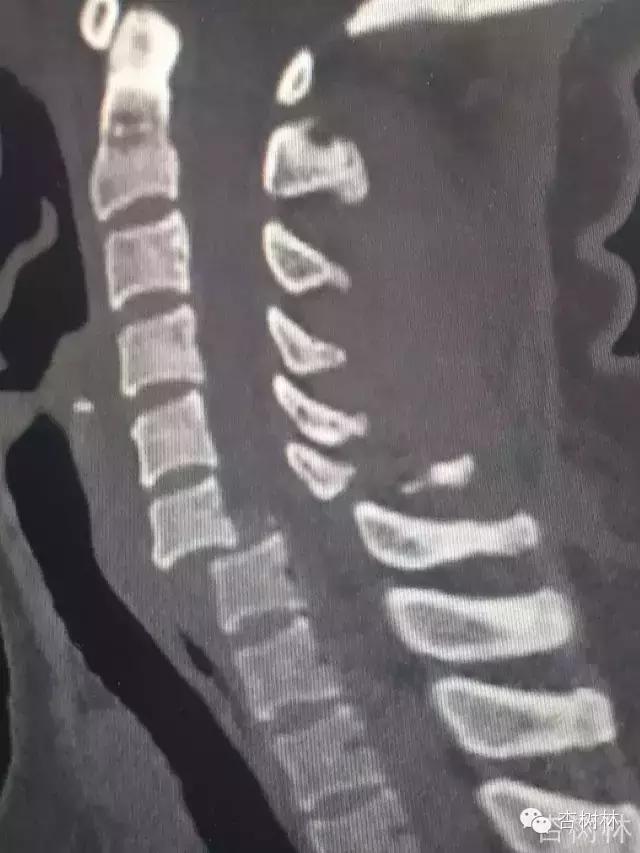

影像:急诊CT及MRI检查提示如下。